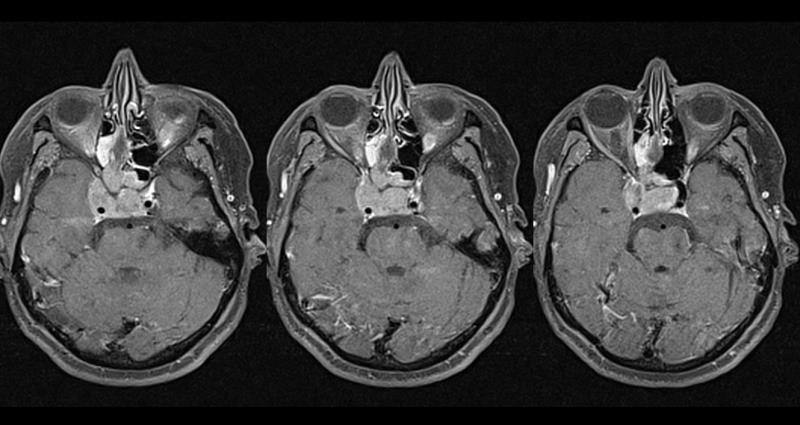

Ασθενής  γυναίκα  64 ετών, προσήλθε με έντονο άλγος στην περιοχή της κάτω γνάθου, ρινική συμφόρηση και επεισόδια επίσταξης , αιμωδίες και υπαισθησία δεξιού ημιπροσώπου κατανομής V1 και V2 και πλήρη οφθαλμοπληγία  δεξιά. O απεικονιστικός έλεγχος με μαγνητική τομογραφία εγκεφάλου  ανέδειξε εξωπαρεγχυματική εξεργασία η οποία διηθεί και καταλαμβάνει το δεξιό σηραγγώδη κόλπο, τον σφηνοειδή κόλπο, τις δεξιές ηθμοειδείς κυψέλες και   την δεξιά άνω και μέση ρινική κόγχη και επεκτείνεται προς τα αριστερά έως και τον αριστερό σηραγγώδη κόλπο. Η ασθενής υποβλήθηκε σε  συνδυασμένη ενδοσκοπικά υποβοηθούμενη   διαβασική  (transbasal) και δια του σηραγγώδους ( transcavernous ) τροποποιημένη κογχοζυγωματική (modified orbitozygomatic) εξωσκληρίδιο προσπέλαση και αφαίρεση του όγκου η ιστολογική εξέταση του οποίου ανέδειξε αδενοκαρκίνωμα.  Η μετεγχειρητική πορεία της ασθενούς ήταν ομαλή και εν συνεχεία παραπέμφθηκε για περαιτέρω ογκολογική και ακτινοθεραπευτική αντιμετώπιση.

Προεγχειρητικός απεικονιστικός έλεγχος